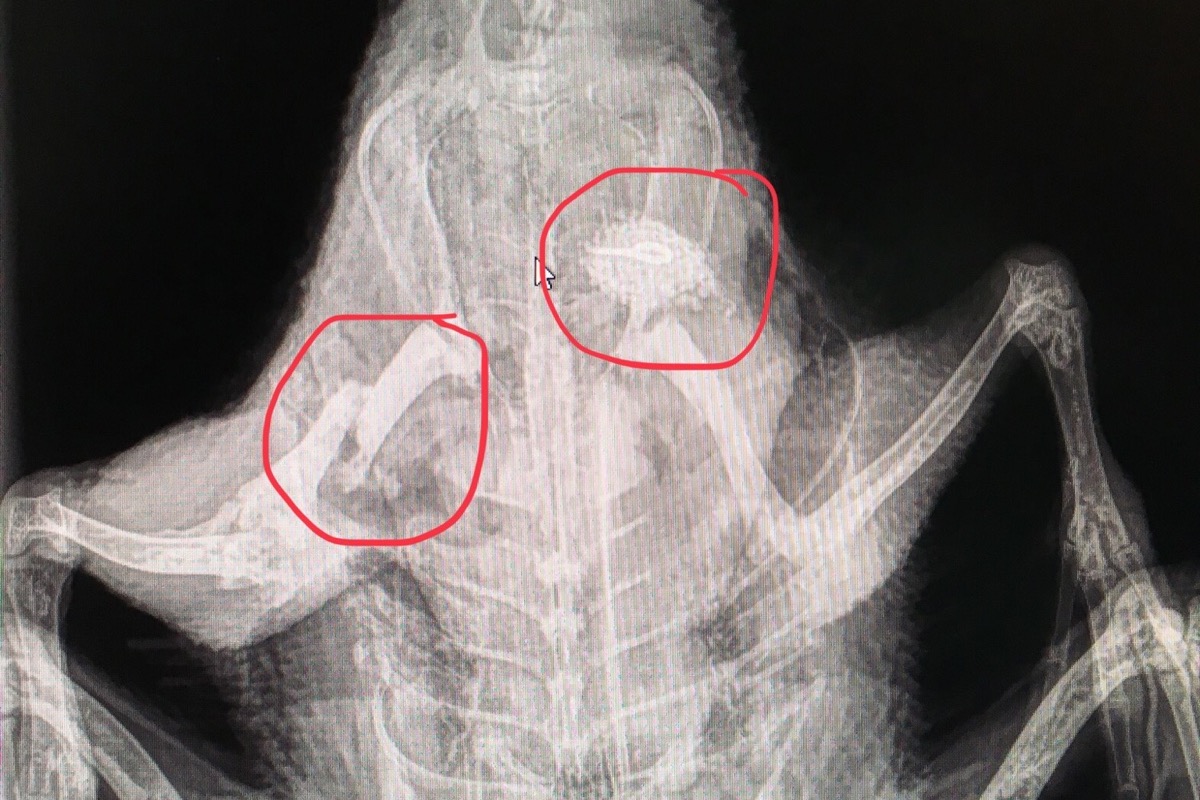

Hi everyone ! So I went to the vet last week for an X-Ray for my duck that wasn’t able to walk anymore. End up she has a fractured leg and a piece of metal in her. The problem is that the vet can’t do anything because the fracture is too high... She can’t make her a plaster... So the only option left is the surgery, that costs around 3000$. I am 16 years old, I can’t pay that. She is a precious pet to me and I want to save her but to do that, I need your help ! Even a 1$ fund can help !As a proof that this is not a scam, the vet’s informations are there: